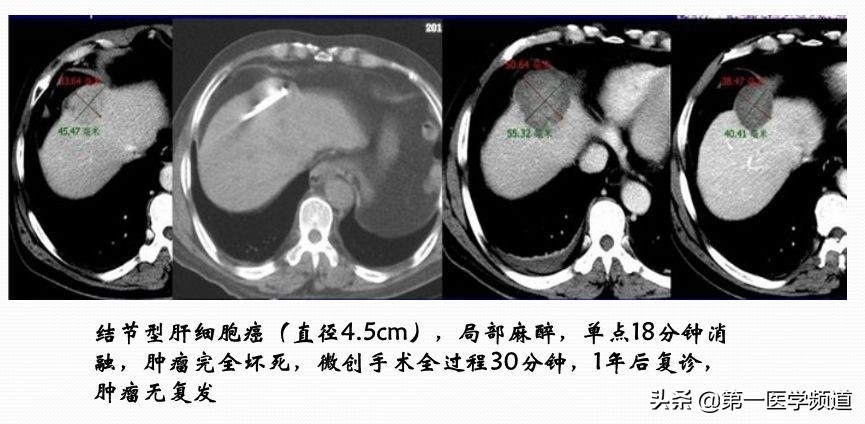

这是一个典型的微波治疗肝癌患者的案例。肝脏内比较大的肿块,接近5cm左右,我们通过8个位点做消融治疗,取得比较好的效果,术后肿瘤完全坏死。